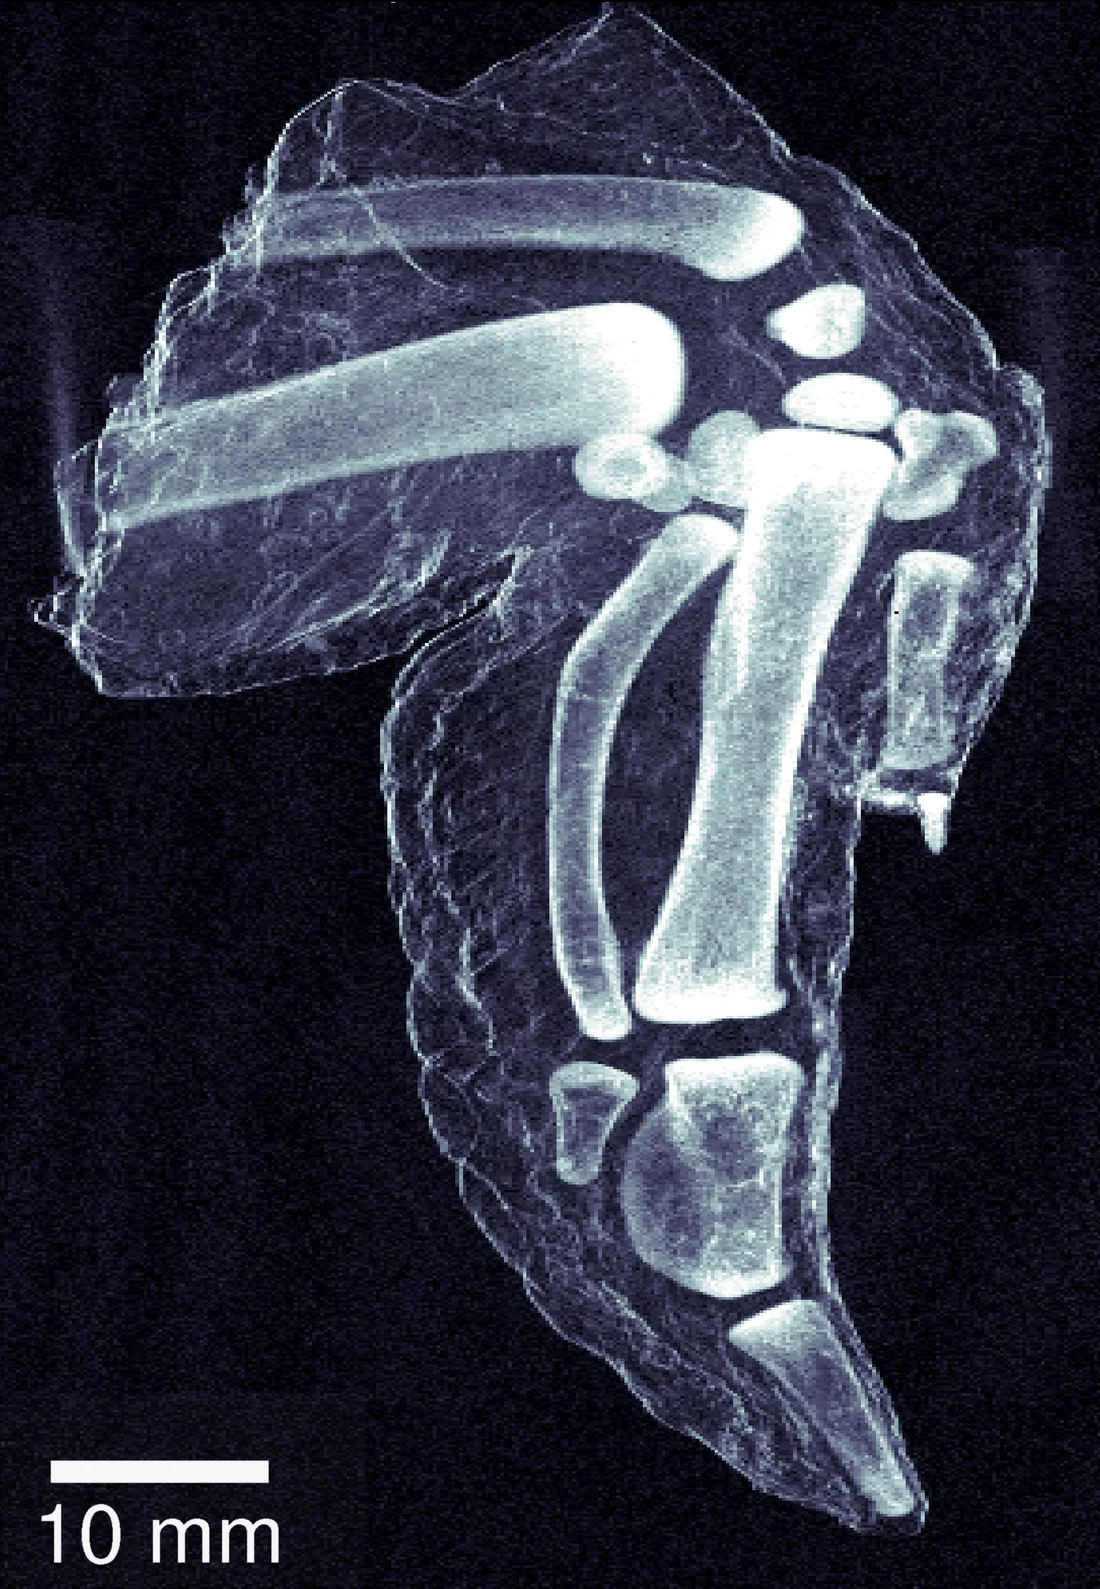

Herkömmliches Röntgenbild eines Hühnerflügels.

Mehr Details sind auf einem Dunkelfeld-Röntgenbild zu sehen.

Im Gegensatz zur herkömmlichen Röntgentechnik, bei der nur die Kontrastunterschiede angezeigt werden, berücksichtigen Dunkelfeld-Röntgenbilder die Streuungseigenschaften im Inneren von Werkstoffen. Auf diese Weise können vor allem Weichgewebe besser analysiert werden und bereits geringe Strukturveränderungen bei Knochen oder Legierungen werden erkennbar. Dies erlaubt bestimmte Krankheiten wie Brustkrebs oder Alzheimer frühzeitiger und zuverlässiger zu diagnostizieren. Die Methode erleichtert auch die Diagnose von Osteoporose, da die Porosität und winzige Brüche des Knochens im Gegensatz zu den unscharfen herkömmlichen Bildern eindeutig erkennbar sind. Bei Sprengstoffen werden Röntgenstrahlen aufgrund ihrer Mikrokristallstruktur stark gestreut. Dank der neuen Methode können sie auch bei traditionellen Sicherheitsanlagen leichter erkannt werden. Da dieses neue Verfahren die Werkstoffe nicht verändert, fördert es auch winzige Risse und Roststellen in Strukturen wie beispielsweise Flugzeugflügeln oder Schiffsrümpfen zutage.